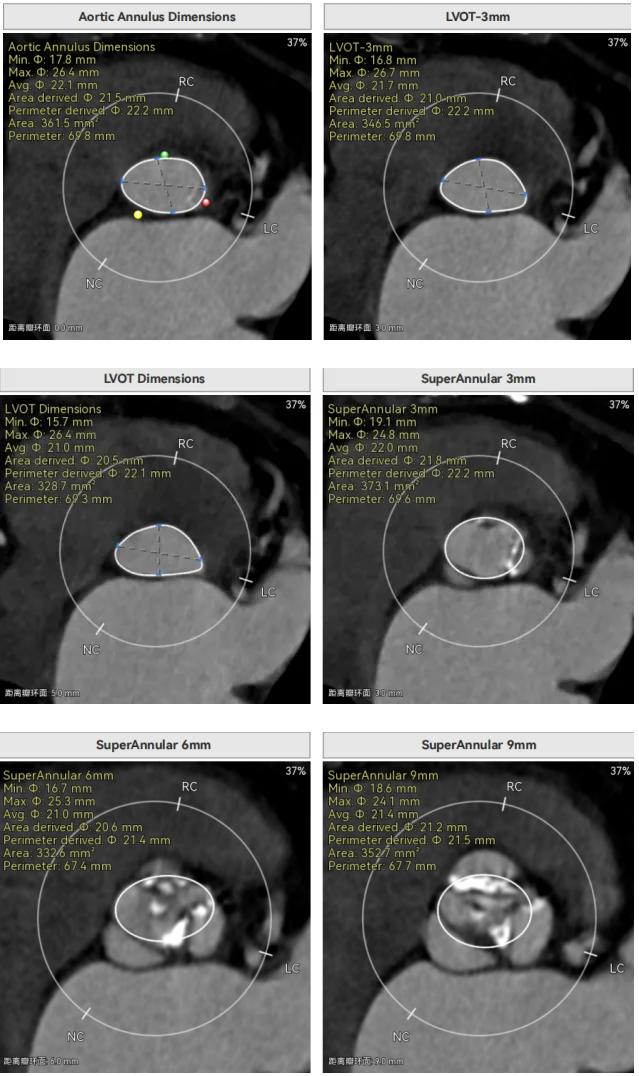

许金鹏教授 安徽省胸科医院 干瓣耐久首选之,15年承诺佑病患:随着病患的复杂性提高及TAVR二次手术窗口期的慢慢到来,摆在临床面前的是如何提升瓣膜使用的耐久性?预装干瓣的获批上市无疑为临床提供了全新的选择。预装干瓣摆脱了传统戊二醛保存的束缚,通过专利抗钙化技术及干式保存工艺打造了一款兼具“曲柔性”和“不沾钙”瓣叶的介入瓣,预期会有更耐久的使用寿命。此次病例患者小瓣环,Prostyle A®自膨瓣的收腰设计,为冠脉开口预留了“生命通道”,而平衡的收腰设计又很好的保证了开口面积,为小瓣环患者血流动力学提供的牢靠的保障。 期待这样一款基于临床需求的性能平衡的耐久干瓣,护佑 TAVR广大患者的全生命周期管理! 患者病史 主要诊断:非风湿性主动脉瓣狭窄(重度);非风湿性主动脉瓣关闭不全(中度);非风湿性二尖瓣关闭不全(中度);心脏扩大(左房明显扩大、左室略大);肺动脉高压(估测肺动脉收缩压约 39mmHg);胸椎压缩性骨折(T9 椎体,考虑新鲜);肺部阴影(两肺慢支改变、多发结节);胆囊术后; 入院检查:BP 109/60mmHg、心率 77 次 / 分(律齐),神清精神可,口唇不绀。 术前超声提示 主动脉瓣钙化并狭窄(重度)伴反流(中量),Vmax509cm/s,PGmax105mmHg;升主动脉增宽;左房明显增大,左室略大;二尖瓣关闭不全伴反流(中+量);瓣尖轻微增厚;室间隔增厚; 术前CT 三叶瓣(L-N融合,功能型二叶瓣),瓣叶增厚中度钙化,钙化主要分布在左冠窦瓣叶边缘及左无融合处、右冠瓣叶基底及边缘,主动脉瓣环径22.2mm,LVOT21.1mm,呈略直通型;双侧冠脉开口高度可,窦部空间大,VTC距离够,预估冠脉低风险,STJ、升主动脉内径可;左室内径可,主动脉水平夹角47°,非横位心。主动脉弓角弓距可;外周入路无明显迂曲,无钙化,两侧股动脉内径可,均可通过20F大鞘,右股低分叉。 手术策略 推荐右侧股动脉为主入路,左侧股动脉为辅助入路,使用20F大鞘,右股分叉上方1cm穿刺。推荐选择AV23瓣膜,18mm球囊预扩,最终理想位置瓣下2mm。 手术过程 在右股动脉穿刺建立通路后,顺利送入大鞘,经食道超声及血管造影确认路径稳定。18mm球囊预扩后评估冠脉灌注良好,后将Prostyle A® AV23瓣膜精准释放于目标位置,超声显示无瓣周漏,术后即刻造影显示无明显反流,导管测平均跨瓣压差8mmHg,心功能明显改善,患者生命体征平稳。 主动脉根部造影 18号球囊预扩 输送器顺利过弓 迅速锚定,平稳释放至工作位 最终造影,位置形态良好,无瓣周漏 Prostyle A®预装干瓣——助力临床最优化解决方案 预装干瓣 便捷顺安:金仕生物专利抗钙化技术运用纳米技术去除组织内的细胞碎片和磷脂,封闭游离醛基,从根本上阻断了瓣膜钙化的多项因素,显著提升了瓣膜的耐久性;同时,相比较传统戊二醛保存方式,干式存储最大限度的保留心包的亲水亲油平衡,还原组织天然曲柔性,进一步保障了瓣叶开合,保证长期耐久性; 流入端桶状设计:流入端桶状的设计,迅速稳定锚定,减少手术时间的同时进一步保障了术中安全; 平衡的收腰设计:该病例左冠高度10.8mm,AV23瓣膜的平衡收腰设计既确保了冠脉开口安全性,又保证了EOA,有效降低了循环崩溃风险,而术后8mmHg的压差的表现更加证明了优秀的血流动力学,进一步提高了瓣膜的耐久性。 专家简介 许金鹏 安徽省胸科医院(点击查看专家详细简历) · END ·